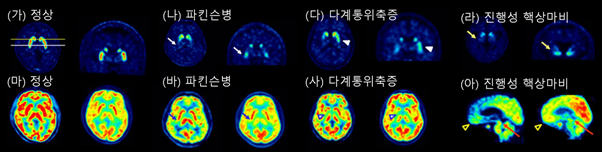

파킨슨병은 도파민 신경세포의 감소가 일어나는 질병으로, 뇌의 도파민 신경에 있는 도파민운반체 (dopamine transporter) 밀도를 측정하는 양전자 단층촬영을 통해 진단의 정확도를 높일 수 있다 (그림 4). 이 검사는 도파민을 생성하는 신경세포의 시냅스 전 종말의 도파민운반체에 결합하는 방사성 추적자를 사용하여, 흑색질-선조체 경로(Nigrostriatal pathway)의 도파민 감소를 확인한다. 흑색질 치밀부 신경세포 약 30% 소실 및 선조체 말단 기능의 50–70% 소실이 발생할 경우 운동증상이 나타난다는 보고가 널리 인용되어 왔다.

최근 정량 영상·모형 연구에서는 양전자 단층촬영을 통한 진단 초기의 도파민운반체 저하가 평균 35–45% 수준으로 추정된다는 분석도 제시된다.

파킨슨병과 정상 (혹은 본태성 떨림, 약물유발 파킨슨증)을 구분하는데 있는 도파민운반체 양전자 단층촬영의 민감도·특이도가 97.4%~100% 정도로 높다. 실제로 체계적 문헌고찰에서 임상 진단 대비 민감도 79–100%, 특이도 97–98% 범위가 보고되었다. 반면 파킨슨병과 비정형 파킨슨증후군 사이의 세부 감별은 있는 도파민운반체 양전자 단층촬영만으로는 신뢰도가 낮다. 파킨슨병과 비정형 파킨슨증후군의 구분을 위해서는 자기공명영상, 뇌 포도당 양전자 단층촬영 (¹⁸F-FDG PET)

등의 추가 검사가 도움이 된다.

(가, 마) 정상인에서의 도파민 운반체 PET(상)과 뇌 포도당 PET(하). (나, 바) 파킨슨병 환자에서 관찰되는 선조체 도파민 운반체 신호의 비대칭적 감소와 비교적 보존된 뇌대사. (다, 사) 다계통위축증 환자에서의 도파민 운반체 신호 광범위 저하와 기저핵·소뇌·교뇌의 대사 저하. (라, 아) 진행성 핵상마비 환자에서의 도파민 운반체 감소 및 전두엽·중뇌의 대사 저하 소견.

뇌 포도당 양전자 단층촬영은 도파민 신경세포의 말단이 아니라 뇌 전체의 대사 패턴을 보여 주므로, 파킨슨병과 비정형 파킨슨증후군의 감별을 하는데 강점이 있다. 조기, 경증 파킨슨병에서 FDG-PET은 정상에 가까우며, 인지 저하가 동반되면 두정엽, 후두엽의 대사 저하가 나타날 수 있다. 진행성 핵상마비는 미상핵, 전두부, 중뇌의 대사 저하가 특징이다. 다계통위축증에서는 기저핵, 소뇌, 교뇌의 대사가 저하된다 (그림 4).